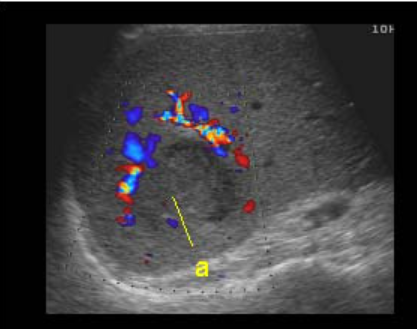

⑤ cavernous hemangioma(혈관종)

정맥의 혈액으로 채워진 여러 개의 작은 혈관에 혈류의 흐름이 느려져 혈전이 형성된 후 종괴처럼 보이는 것을 혈관종이라고 한다. 간의 양성종양 중 가장 흔한 질환이다. 초음파상 우연히 발견되며 거의 증상이 없다. 여성에서 5배 더 흔하고 분만경험이 있는 30-40대 여성에 많이 발견된다. 대부분 단발성으로 우측 간의 피막하나 혈관주위에 발생한다.

US finding

- 2cm 이하는 내부 균일한 고에코 종괴로 보인다

- 3cm 정도 되면 내부에코가 약간 저하된 종괴로 보인다

- 5cm 이상은 고에코와 저에코가 뒤섞인 복합성 에코종괴로 보인다

- color doppler 검사 시 내부 혈액의 흐름이 없다

- 환자의 자세를 바꾸면 에코가 저하된다(chameleon sign )

- 프로브로 압박하면 에코가 달라진다 (disappering sign)

- 시간이 경과함에 따라 내부에코의 변화(wax and wane sign)